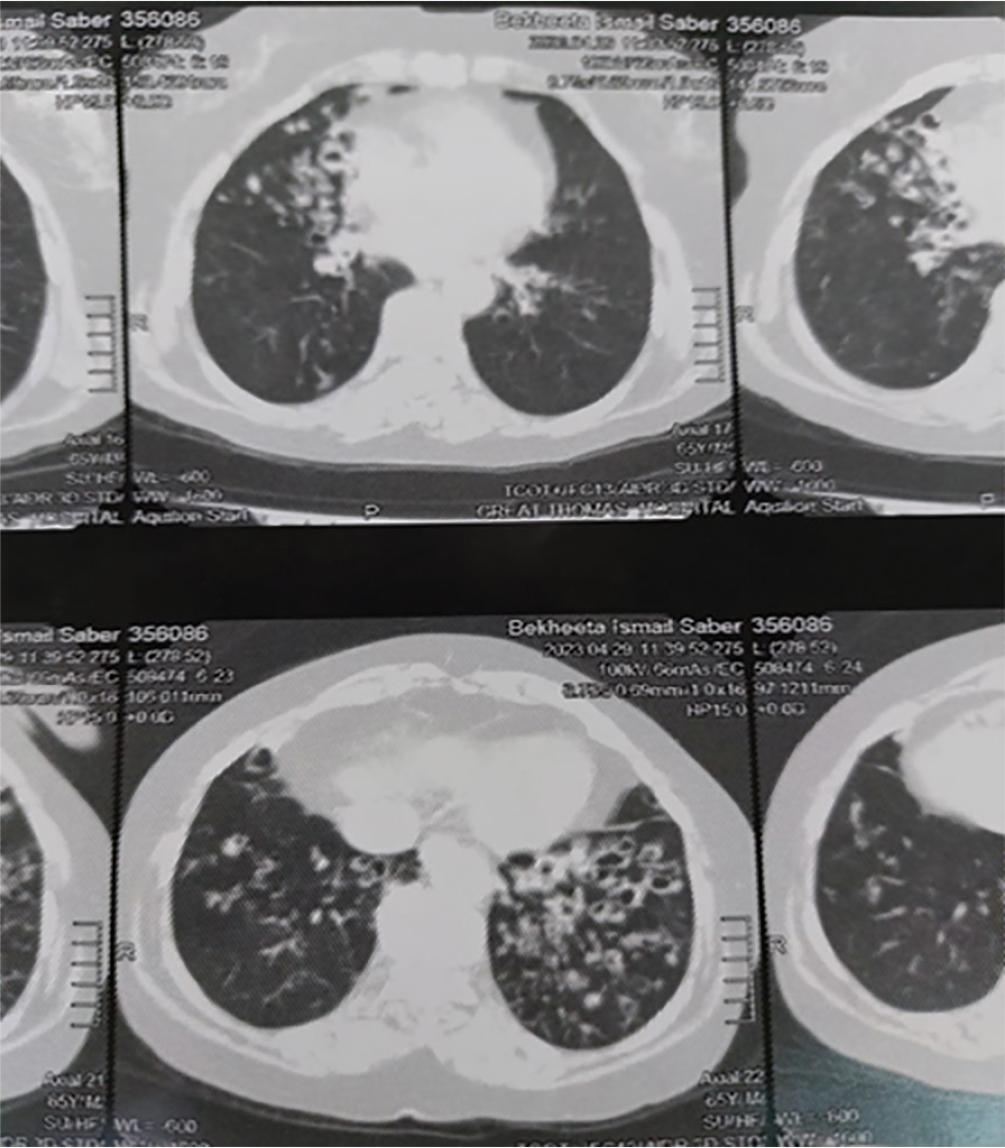

As regard the correlation between BSI score & FACED score and laboratory findings, we found that there was significant positive correlation between BSI & FACED scores and white blood cell count, ESR, and serum fibrinogen level (Table 3). Patients with bronchiectasis had a high plasma fibrinogen level, and the serum fibrinogen level was significantly increased with increasing severity of BSI & FACED scores (P-value = <0.001 for both) (Figures 2,3,4 and 5).

Cystic bronchiectasis.

Cylindrical bronchiectasis.